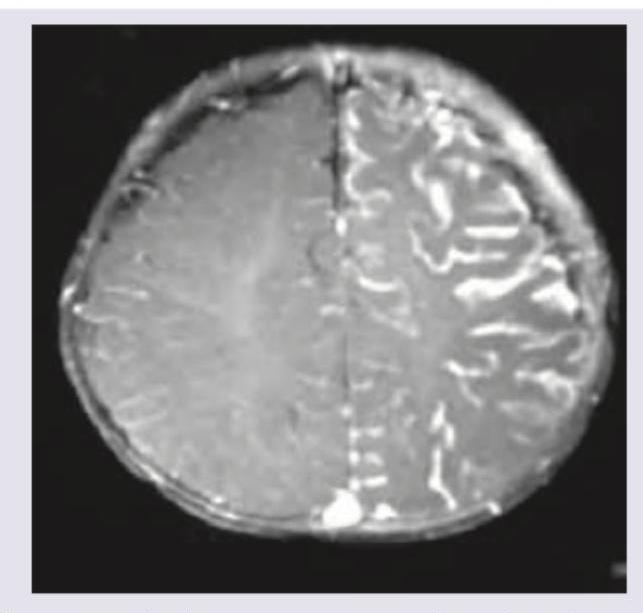

A 30-year-old male patient presents to OPD with complaints of recurrent headache and nausea, MRI of brain shown below. What is the diagnosis?

Explanation: ***Meningioma*** - The MRI displays a classic **extra-axial mass** (meaning outside the brain parenchyma) arising from the convexity dura. - Key imaging features supporting this diagnosis are the **well-circumscribed, lobulated shape** and the **intense, homogenous enhancement** post-contrast. *Glioma* - Gliomas, such as **Glioblastoma Multiforme (GBM)**, are **intra-axial tumors** (arising within the brain tissue) and typically have irregular, infiltrating margins. - High-grade gliomas commonly show **ring enhancement** with central necrosis, which is not characteristic of the lesion depicted. *Ependymoma* - Ependymomas are typically found within the **ventricular system** (especially the fourth ventricle in adults, or lateral ventricles in children) or the spinal cord. - They are **intra-axial** tumors (ventricular location being the defining feature) and rarely present as extra-axial convexity lesions. *Pilocytic astrocytoma* - This tumor is predominantly seen in children and adolescents, often located in the **cerebellum** or along the optic pathways, usually presenting as an **intra-axial** tumor. - Radiologically, it typically appears as a large **cyst with an enhancing mural nodule**, which differs significantly from the solid, extra-axial lesion shown.